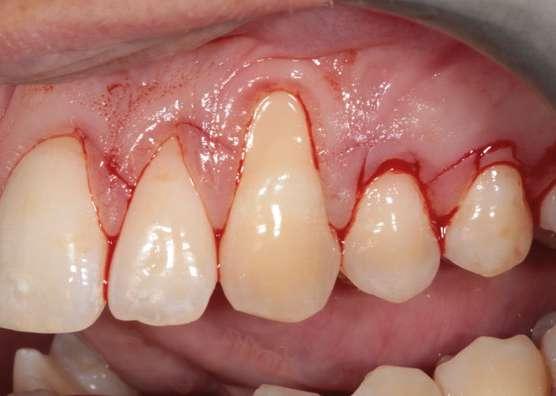

Fase quirúrgica y restauradora

Después de un detallado análisis y valoración de las alternativas terapéuticas, se planificaron 2 procedimientos quirúrgicos mediante colgajos de avance coronal con acceso lateral y sin descargas para el tratamiento de las recesiones del maxilar superior (Fig. 2) (7-9).

A continuación procederemos a describir el paso a paso del tratamiento quirúrgico de las recesiones (Figs. 2 a 7). Ambos procedimientos quirúrgicos se realizaron bajo anestesia local y sedación consciente por vía endovenosa y con un tiempo de descanso para el paciente entre procedimientos de 1 mes y medio. En este caso, el eje de rotación fueron los caninos en ambos lados y todas las incisiones para-marginales oblicuas (líneas punteadas en rojo) se realizaron hacia estos dientes (Fig. 2).

Figura 2. Planificación quirúrgica.

Figura 4. Diseño de las incisiones y del colgajo. Nótese la creación de una “falsa recesión” en

colgajo al finalizar el avance coronal.

Figura 3. Situación clínica el día de la intervención quirúrgica.

Figura 5. Colgajo elevado “Split-Full-Split” y fijación de los injertos de tejido conectivo con suturas 7/0 reabsorbibles (PGA).

Figura 7. Post-operatorio y excelente curación 7 días después de la cirugía.

Figura 6. Avance coronal sin tensión y sutura del colgajo mediante puntos “sling” con sutura 6/0 reabsorbible (PGA).

Cada incisión oblicua debía permitir el correcto movimiento lateral y coronal de la punta de la papila quirúrgica hacia su papila anatómica correspondiente. Las incisiones para-marginales oblicuas debían conectar la parte más apical de la recesión con un punto final ubicado en la base de la papila de los dientes vecinos. La altura de este punto final se midió desde la punta de la papila y corresponde a la altura de la recesión + 1 mm. Adicionalmente, para permitir llevar a cabo un colgajo sin descargas, conseguir el suficiente avance coronal a nivel de 2.3, así como una buena adaptación del colgajo en premolares, se realizaron “falsas recesiones” (10) a nivel de 2.4 y 2.5 (Fig. 4). Finalmente, y de acuerdo con los estudios de Stefanini y colaboradores (9), se planificó aplicar el injerto de tejido conectivo (ITC) de manera sitio-específica en los dientes 1.3 y 2.3 debido a la presencia de una banda de encía queratinizada apical a la recesión ≤ 1 mm (Fig. 2 y 5).

La elevación y preparación del colgajo incluyó un abordaje “split-full-split”. En primer lugar, se elevaron las papilas quirúrgicas a espesor parcial utilizando hojas de bisturí 15C. Luego, se realizó la elevación a espesor total en el tejido queratinizado apical a la recesión para exponer aproximadamente 3 mm de hueso apical a la dehiscencia ósea (se puede ver el área de exposición ósea apical a las recesiones) (Fig. 5).

Finalmente, se realizaron incisiones profundas y superficiales para disecar la porción apical del colgajo. La incisión profunda se hizo paralela al hueso en dirección apical para desprender las inserciones musculares del periostio, mientras que la incisión superficial se realizó paralela a la mucosa de revestimiento para liberar el epitelio del tejido conectivo y de las inserciones musculares.

La curación fue excelente y los puntos de sutura se retiraron a las 3 semanas post-operatorias (Fig. 7).

Seguimiento y evolución del caso

Se presentan fotografías clínicas de la evolución y seguimiento a 6 meses, 12 meses y a 5 años (Figs. 8-10). A pesar de una mínima recidiva de menos de 1 mm en la recesión del diente 2.1, es interesante y reconfortante observar la gran estabilidad clínica de los tejidos blandos, así como un color, textura y forma muy armónicos de toda la encía tratada. En gran parte también gracias a un excelente cepillado y mantenimiento periodontal.